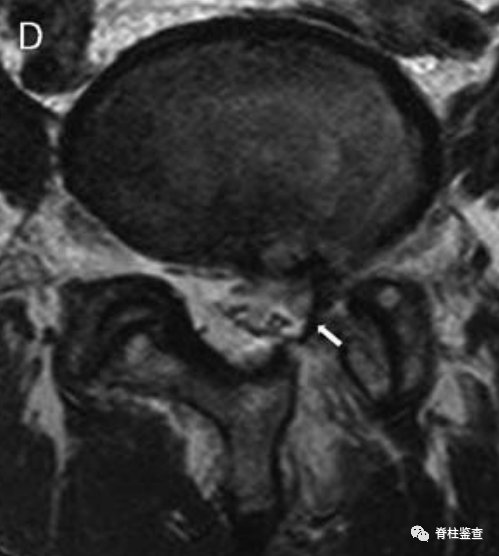

术后减压良好,硬膜囊再扩张(白色↓)。

术后第1天显示,椎间盘充分移除;MR图像中的瘢痕组织限制了硬膜囊的充分扩张(白色↓)。